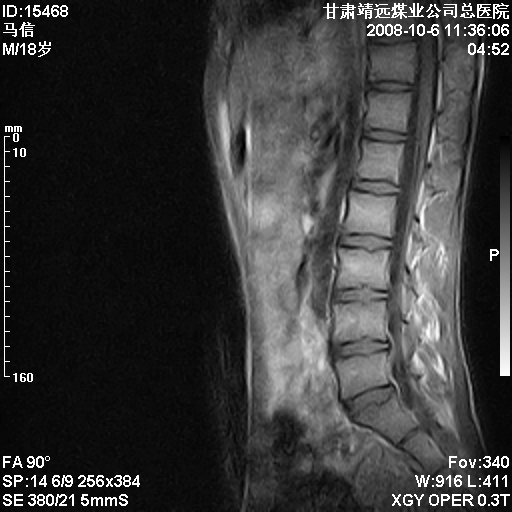

患者18岁,学生,在玩耍中受伤来检查,患者喜欢打篮球。颈椎内异常信号影,我们考虑占位,但是不像占位,又考虑硬膜囊的增厚,大家关建看颈椎椎管内的那个异常占位信号

腰椎的改变是不是正常发育的改变,还是打篮球的长期慢性损伤。

考虑 c3-4 c4-5 c5-6椎间盘突出,l3-4 l4-5 l5-s1椎间盘变性

颈椎建议做增强扫描;腰椎诸椎终板骨骺炎。

后纵韧带增厚,颈2/3、3/4、4/5、5/6椎间盘变性、突出;椎体有旋转,提示椎小关节有问题;腰椎间盘变性,许莫氏结节。

后纵韧带增厚,颈2/3、3/4、4/5、5/6椎间盘变性、突出;椎体有旋转,提示椎小关节有问题。腰椎诸椎体终板骨骺炎可能性大!支持!